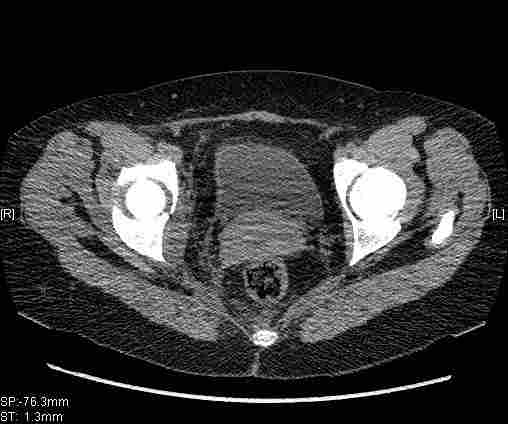

Удалось сегодня вывести пациентку в соседнюю больницу, где есть кт. Срезы сделаны только горизонтальные.

|